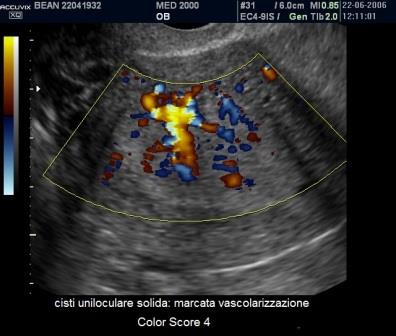

Per quanto riguarda le neoplasie abbiamo visto come il corpo luteo cistico può assumere l'aspetto di una Cisti Uniloculare Solida dove la componente solida è rappresentata dal coagulo endocistico. Un valido aiuto nella diagnosi differenziale ci è dato dal power-Doppler che ci consente di valutare le differenze di vascolarizzazione tra Cisti Luteinica e Cisti Uniloculare Solida di altra natura. La Cisti Luteinica ha una componente solida endocistica rappresentata dal coagulo che non è vascolarizzato al power-Doppler mentre presenta una parete riccamente vascolarizzata (ring of fire). Le Cisti Uniloculari Solide di altra natura possono avere una parete vascolarizzata ma non in maniera così intensa come per il corpo luteo ed hanno una componente solida (papille e parti solide) che può avere un Color Score variablie da 2 a 4.

A margine credo possa essere utile ricordare come si calcola il Color Score. Esso rappresenta una valutazione della vascolarizzazione di una neoformazione annessiale stimata soggettivamente dal medico ecografista secondo una scala che va da 1 a 4:

- Color Score 1: assenza di flusso

- Color Score 2: presenza di pochi spots vascolari

- Color Score 3: presenza di una discreta vascolarizzazione

- Color Score 4: presenza di abbondante vascolarizzazione